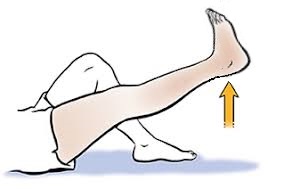

یکی از سادهترین و مؤثرترین تمرینها برای تقویت این عضله، حرکت بالا نگهداشتن پای صاف در حالت خوابیده است که به آن Straight Leg Raising (SLR) گفته میشود.

نحوه انجام تمرین : حتما با همراه داشتن ساعت انجام شود

- روی زمین یا تخت در حالت خوابیده به پشت قرار بگیرید.

- یکی از پاها را کاملاً صاف نگه دارید و زانو کاملا صاف باشد .

- پنجه پا را به سمت صورت بکشید تا عضلات پشت ساق پا نیز کشیده شوند.

- با انقباض عضله چهارسر، پای صاف را از زمین بلند کنید تا پاشنه حدود ۲۰ تا ۳۰ سانتیمتر از سطح زمین فاصله بگیرد.

- پا را در همین حالت به مدت ۱۰ تا ۲۰ ثانیه نگه دارید (بر اساس توانایی شما).

- سپس پا را بهآرامی پایین بیاورید و همین حرکت را با پای دیگر تکرار کنید.

– این تمرین را در طول روز حداقل دو سری 5 باره انجام دهید.

– هر زمان که توانستید بهراحتی پا را برای مدت تعیینشده بالا نگه دارید، زمان نگهداشتن را افزایش دهید (مثلاً از ۲۰ ثانیه به ۳۰ ثانیه).

– هدف نهایی این است که بتوانید پا را با زانوی کاملاً صاف، بدون لرزش و بدون درد، به مدت ۶۰ ثانیه بالا نگه دارید.

این تمرین ساده، بدون نیاز به تجهیزات خاص، میتواند تأثیر بسیار زیادی در آمادگی شما برای جراحی و بهبود سریعتر پس از آن داشته باشد.